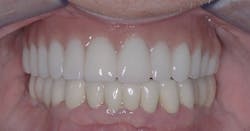

The most well-known implant-supported fixed restoration concept for edentulous patients was taught by Per-Ingvar Brånemark, MD, PhD, more than 30 years ago. Typically, six implants were placed on each arch, located anterior to the sinus on the maxillary and anterior to the mental foramen on the mandibular. When the implants had integrated into the bone over several months, a prosthesis was screwed onto the implants. Cantilevers were extended on each side of the arch, about one centimeter distal to the implant-supported portion of the prosthesis. The prostheses usually included 12 teeth, including the first molar only distally. Overall, these prostheses served well (figure 1). If one or two implants failed, which occasionally happened, the prostheses usually were still viable and functioned adequately.

Figure 1: Patient with maxilla restored with the previous popular concept using six implants as described in the narrative